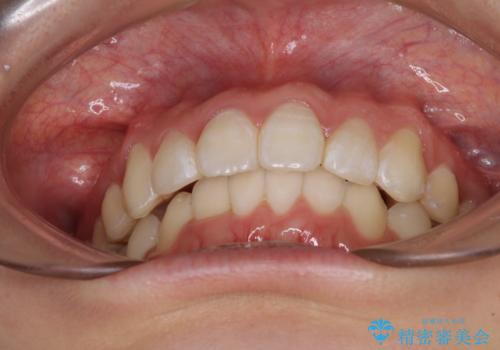

上下前歯の叢生をインビザラインできれいに

- 前歯のデコボコを気にして来院された患者様です。

前歯が重なっていることで口元が閉じにくくなっていたため、歯列全体の側方への拡大と、歯と歯の間を少し削ってスペースを獲得することとしました。

下顎前歯は後戻りを起こしやすいため、舌側を細いワイヤーで固定し、マウスピース型リテーナーで保定を行うこととしました。